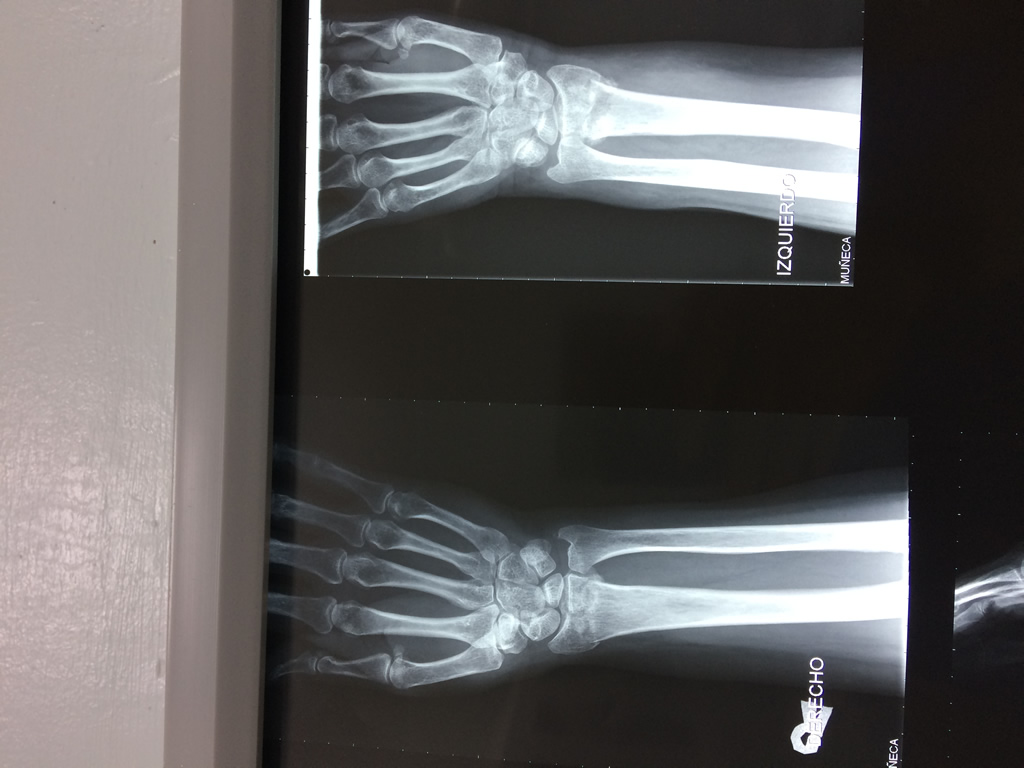

Los procedimientos más comunes en cirugía de la mano son aquellos destinados a reparar traumatismos, incluyendo lesiones de tendones, nervios, vasos sanguíneos, y articulaciones; huesos fracturados; y quemaduras, cortes, y otros daños de la piel.